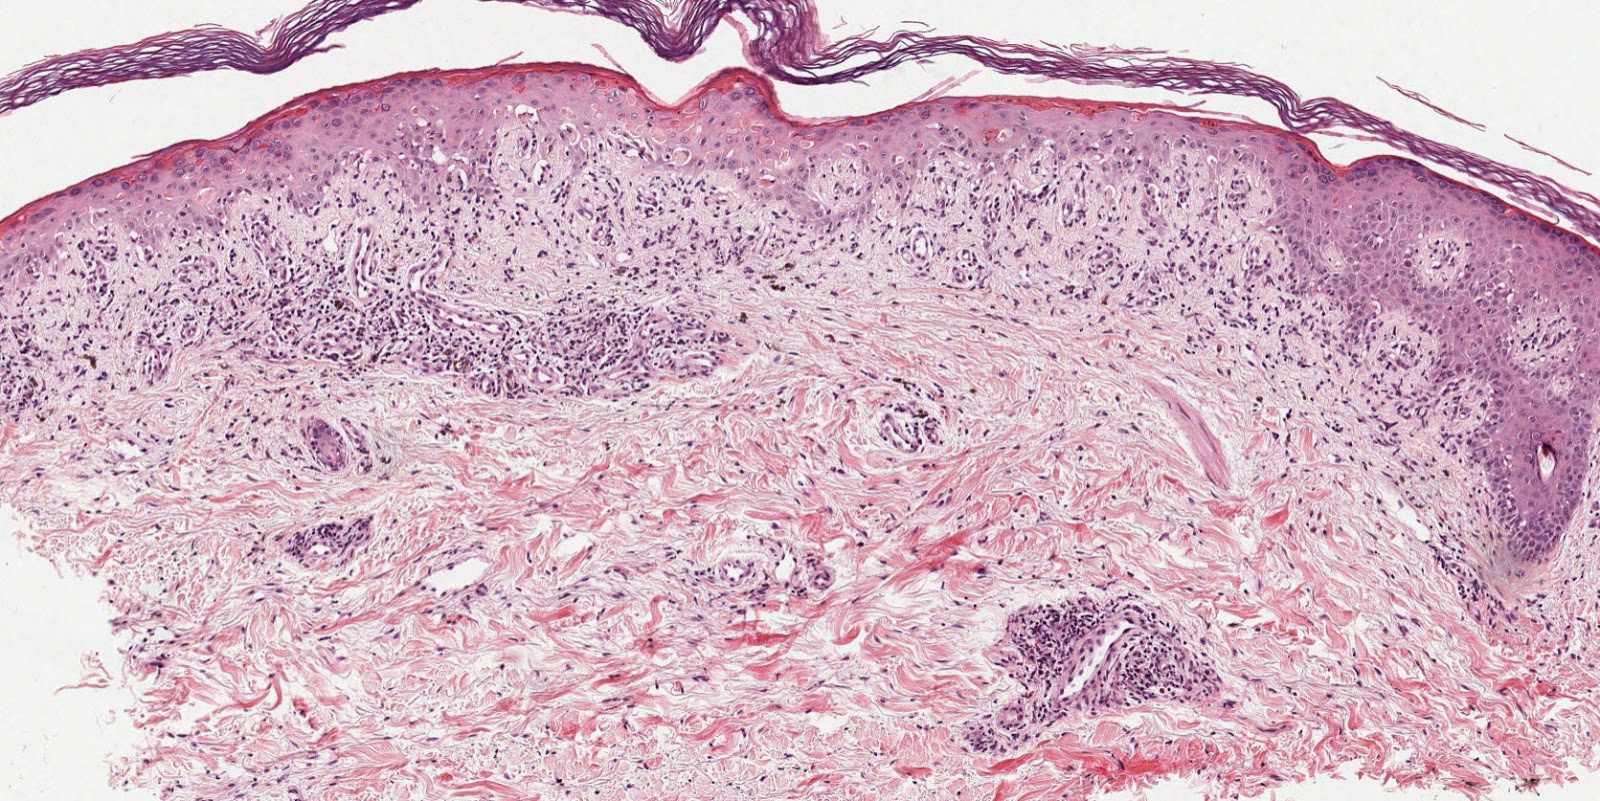

Lichenoid infiltrate

Perivascular infiltrate

Marked basal layer damage is a feature of Erythema multiforme and its variants Stevens Johnson syndrome and Toxic epidermal necrolysis. We call this interface reaction pattern. It may also be seen to a lessor degree in lupus erythematosus and lichen planus and in the PLEVA variant of Pityriasis lichenoides.

Older terms for these changes were liquifactive degeneration and hydropic degeneration.

Lichenoid reaction pattern may overlap here but usually gives less vacuolar changes at the DEJ than interface damage and a more florid lichenoid infiltrate.